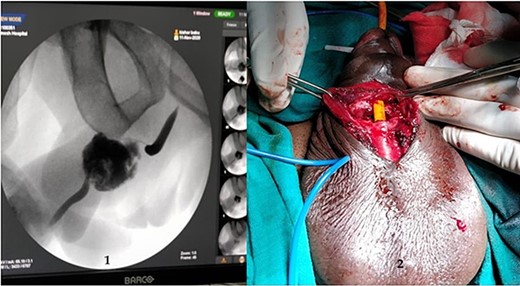

A 37-year-old male presented with a history of a ‘snap’ sound and immediate detumescence of penis during intercourse, when he fell and hit the pubic bone of his partner. There was generalized swelling and pain in the penis. There was acute retention of urine, an attempt to pass a catheter failed and the patient underwent supra-pubic catheterization. On examination, there was classical ‘eggplant deformity’ of the penis with blood at the tip of the meatus. MRI showed a tunical tear on both sides at the penoscrotal junction with indistinct urethra and extensive hematoma in the proximal penile shaft (Fig. 1). With the diagnosis of a fractured penis and possible urethral injury, after proper counselling, the patient was taken up for surgery. On the table, a retrograde urethrogram (RGU) was done showing evidence of partial urethral disruption. On exploration with penoscrotal vertical incision, there was total transection of proximal penile urethra, and a 1.5 cm tunical injury of corpus cavernosum on both sides ventrally (Fig. 2). There was extensive hematoma. Corpora sutured with 4.0 prolene after reconstructing the midline septum. Urethral ends mobilized and anastomosed with 3.0 vicryl in a single layer with minimal spatulation (Fig. 3). The patient was discharged on the 5th post-operative day; Foley catheter was removed on day 21. Follow-up RGU done after 3 months showed no evidence of stricture (Fig. 4).

Reconstruction of midline septum with mobilized and anastomosed penile urethral ends.